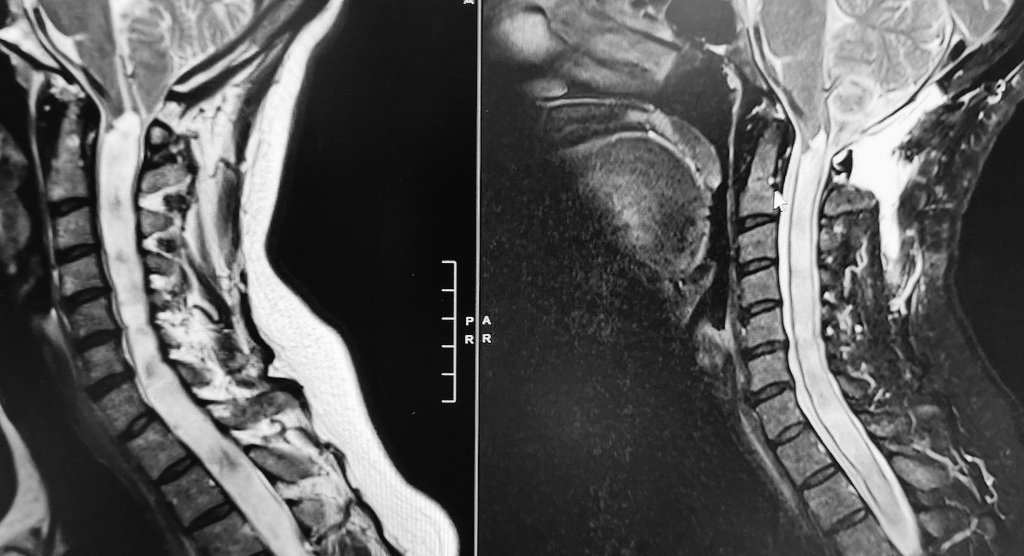

Suboccipital #craniectomy with intraoperative imaging from @bk_Medical #ultrasound showed active decompression of the syrinx. MRI on POD1 already significant improvement! Gotta love #Neurosurgery, rather #cranialneurosurgery - About as close as I like to get to #spinesurgery

@EAMDMD

Edward Duckworth, MD, MS

3 years

None more impressive than this 50ish yo patient with only mild hand parasthesias and relatively modest #cerebellar #ectopia from #chari malformation, but a holocord #syrinx